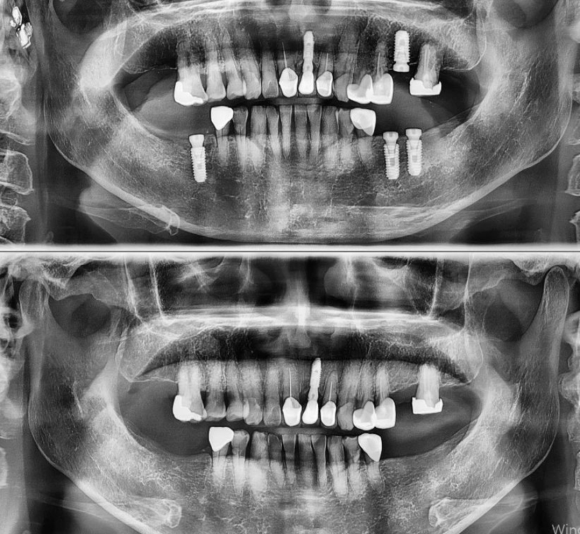

2022.4.5 파주에서 오신분 당일상담 식립. 식립시간 10분. 소문듣고 오는 분들이 많아짐 저희 숭실대 입구역 리더스진 치과는 한달 평균 임플란트 60~100개를 꼼수 없이 가장 좋은 재료와 기술로 원칙적으로 식립하는 치과입니다. #상도동에서임플란트가장많이하는치과

2022.4.5 파주에서 오신분 당일상담 식립. 식립시간 10분. 소문듣고 오는 분들이 많아짐

저희 숭실대 입구역 리더스진 치과는 한달 평균 임플란트 60~100개를 꼼수 없이 가장 좋은 재료와 기술로 원칙적으로 식립하는 치과입니다.